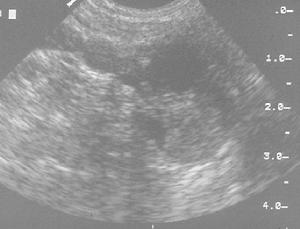

甲狀旁腺腫瘤的超聲定位(二)手術探查和治療 探查時必須詳細尋找四枚腺體,以免手術失敗。術中需作冰凍切片鑑定。如屬腺瘤,應切除腺瘤,但須保留一枚正常腺體:如屬增生,則應切除其三,第四枚腺體切除50%左右。異位的腺體,多數位於縱膈,可順沿甲狀腺下動脈分枝追蹤搜尋,常不必打開胸骨。如手術成功,血清甲狀旁腺激素濃度及血、尿鈣、磷異常代謝可獲得糾正,血磷可於術後迅速升至正常,而血鈣亦可在1~3天后下降至正常範圍內。在伴有明顯骨病者,則因術後鈣、磷大量沉積於脫鈣的骨骼,血鈣可於術後1~3天內降至過低水平(5~8mg/dl),反覆出現口唇麻木和手足搐搦,可靜脈注射10%葡萄糖酸鈣10ml,每日2~3次,有時每日需要量可多至100ml或30~50ml溶於500~1000ml5%葡萄糖液內靜脈點滴,症狀於3~5天內可得改善。如低鈣持續1月以上,提示有永久性甲狀旁腺功能減退可能,需補充維生素D。如補鈣後,血鈣正常而仍有搐搦,尚需考慮補鎂(詳見甲狀旁腺功能減退症)。手術成功後血鈣、磷多數可望在一周內恢復正常,但鹼性磷酸酶則在骨骼修補期間,可長期持續升高。手術後如有復發、則需再次手術。